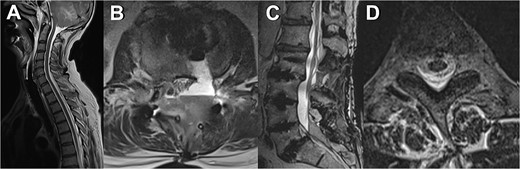

The patient was admitted to the intensive care unit, cardiopulmonary stable but without awakening response after sedation cessation. Cranial MRI revealed basal subarachnoid hemorrhage, significant cerebellar vasogenic edema, swelling of the posterior cranial fossa, tonsillar descent, and ventricular compression, indicative of pseudohypoxic brain swelling due to CSF loss (as seen in Fig. 1). The surgical drainages were delivering no signs of CSF loss. An external ventricular drain (EVD) was placed for brain pressure compensation showing a clear appearing CSF with an opening pressure over 20 mmHg. A conservative intracranial pressure therapy with mannitol and deepening of sedation was initiated. Subsequent CT imaging showed progressing global brain edema and cerebellar and basal ganglia infarcts. The following cranial and spinal MR Imaging showed an extensive CSF leakage with wide epidural spread, necessitating revision surgery to cover a 4-mm dural tear at the lumbar level L2/3 by stitching over the dura and applying a Tachosil sponge (as seen in Fig. 2).

MRI scans depicting various manifestations of liquor leakage; (A) TSE sagittal view of the cervical spine, illustrating fluid distribution and spinal alignment; (B) axial view at the level of the third thoracic vertebra (T3), showing detailed cross-sectional anatomy, and (C) T2-weighted sagittal view, highlighting the spinal cord and surrounding structures; (D) axial view at the level of the second and third lumbar vertebrae (L2/3), providing insights into lower spinal segments.